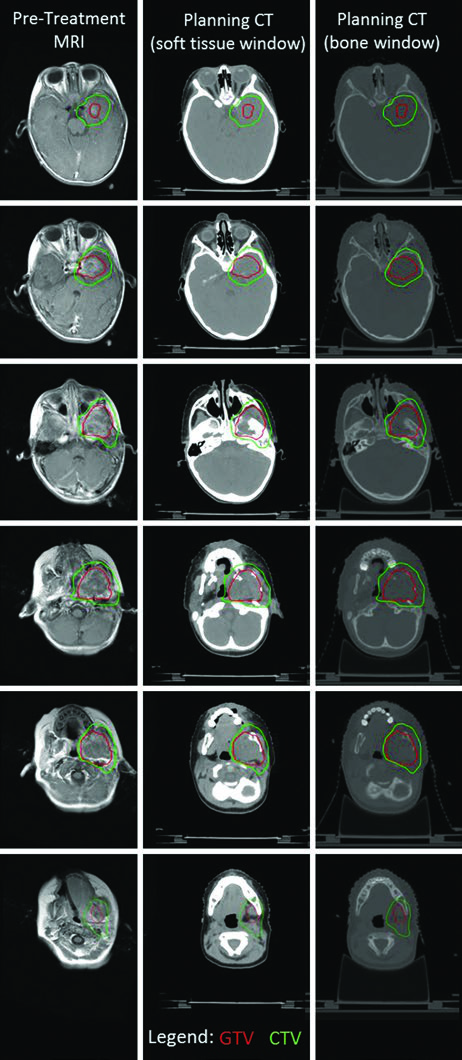

O caso de RMS parameníngeo da fossa infratemporal ilustra a complexidade do delineamento em lesões com extensão intracraniana. A fusão de RM T1 pós-contraste com TC de simulação permitiu identificar tanto a invasão intracraniana quanto a erosão óssea da mandíbula e da placa pterigoide esquerda. A extensão intracraniana motivou o início precoce da terapia local concomitante à quimioterapia, com tratamento em dose única. Máscara termoplástica e guiamento diário por kV permitiram margem de PTV de apenas 3 mm, e o PTV recebeu 50,4 Gy.

O tipo e frequência de guiamento por imagem determinam a margem CTV-PTV. Muitas instituições utilizam kV diário e consequentemente margens de PTV de 3 a 5 mm. Margens menores podem ser consideradas em cenários com guiamento mais robusto ou proximidade de estruturas críticas — situação frequente em sarcomas de cabeça e pescoço, onde nervos ópticos, tronco encefálico e outras estruturas estão próximas aos volumes-alvo. A simulação por RM pode complementar a TC para fornecer dados de RM na posição de tratamento. Em pacientes mais jovens — geralmente abaixo de 8 anos — sedação ou anestesia diária pode ser necessária. Para planejamento de outros tumores pediátricos no SNC que também requerem imobilização rigorosa, confira nosso artigo sobre tumores cerebrais pediátricos.